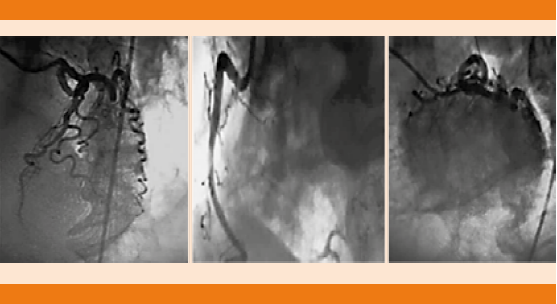

Paciente femenina de 68 años de edad, con antecedente de hipertensión arterial sistémica y cirugía de clipaje por hemorragia subaracnoidea 14 años antes. Ingresó por pérdida del estado de alerta, crisis convulsivas tónico-clónicas generalizadas y deterioro neurológico con puntaje de acuerdo con la escala de coma de Glasgow de seis puntos a expensas de: respuesta ocular: un punto, respuesta verbal: dos puntos y respuesta motora: tres puntos, de 12 horas de evolución. A su ingreso en el servicio de Urgencias se decidió dar manejo avanzado de la vía aérea, vasopresor e inotrópicos, así como cuidados de paciente neurocrítico. La tomografía de cráneo simple evidenció imagen hipodensa en la región frontotemporal derecha sugerente de infarto que correspondía al territorio de la arteria cerebral media derecha y cambios posquirúrgicos asociados (Figura 1). El electrocardiograma de 12 derivaciones mostró desnivel positivo en la cara anterior extensa, lesión subepicárdica en la cara anterolateral extensa, desnivel negativo en la cara inferior, lesión subendocárdica inferior, sin datos de isquemia o necrosis (Figura 2). Biomarcadores de lesión cardiaca: troponina 2.1, CK 232, CK-MB 33. Por los cambios encontrados en el electrocardiograma y el incremento de biomarcadores cardiacos se realizó coronariografía en la fase aguda para excluir oclusión coronaria que reportó ausencia de lesiones estenóticas o placas de ateromas en la circulación coronaria derecha e izquierda. En los ventriculogramas se observó dilatación apical fija e hipocinesia con movilidad conservada en las bases. Insuficiencia mitral leve. Presión telediastólica del ventrículo izquierdo de 18 mmHg y fracción de eyección del ventrículo izquierdo de 40% (Figura 3). El desenlace de la paciente lamentablemente fue funesto.

Figura 3 Coronariografía con los siguientes hallazgos: tronco bifurcado sin lesiones, descendente anterior que irriga hasta el ápex cardiaco, con tortuosidad severa y flujo lento coronario, sin lesiones. Circunfleja no dominante con tortuosidad severa y flujo lento, sin lesiones, coronaria derecha dominante sin lesiones. En los ventriculogramas (oblicua derecha e izquierda) se observa dilatación apical fija con movilidad conservada en las bases. Insuficiencia mitral leve. Presión telediastólica del ventrículo izquierdo 18 mmHg, FEVI 40%.